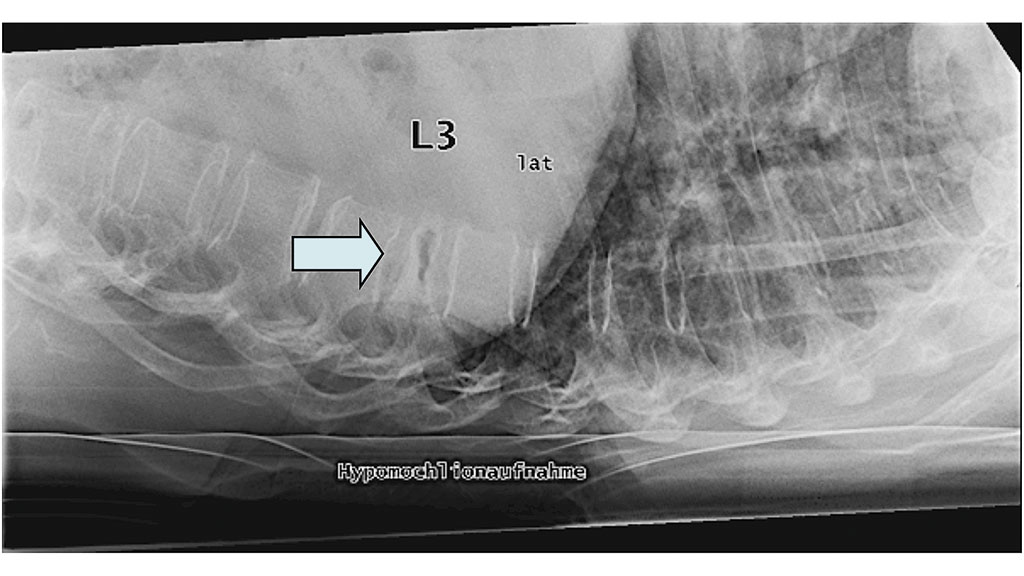

Bildgebende Standarddiagnostik ist die nativradiologische Darstellung des betroffenen Wirbelsäulenabschnittes in zwei Ebenen. Bei diagnostizierter Fraktur (Abb. 1) sollte bei Verdacht auf eine alte Wirbelkörperfraktur zusätzlich nativradiologisch eine Hypomochlionaufnahme (Abb. 2) im Liegen angefertigt werden, um erste Hinweise auf eine mögliche Wirbelkörperpseudarthrose zeitnah zu erhalten. Weiterführend wird mittels Magnetresonanztomografie (MRT) geklärt, ob es sich um eine frische Fraktur handelt (Steigerung der Intensität in den STIR- oder TIRM-Sequenzen) (Abb. 3) und ob möglicherweise ligamentäre Strukturen verletzt sind, um eine mögliche B- oder C‑Verletzung (nach AO: Arbeitsgemeinschaft Osteosynthese) der Wirbelsäule nicht zu übersehen. Gegebenenfalls wird die Diagnostik mittels Computertomografie (CT) vervollständigt, um die Frakturform exakt evaluieren und klassifizieren zu können. Echte Operationsindikationen sind Berstungsfrakturen der Wirbelkörper sowie B- und C‑Verletzungen der Wirbelsäule 22.